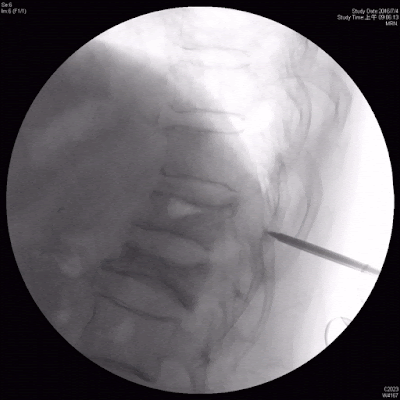

目前的X光, 骨水泥並不是很完整灌在脊椎椎體裏頭,有些滲漏到第十二胸椎及第一腰椎之間的椎間盤,有些滲漏到椎體前方及右側

我緊急安排了電腦斷層(CT)以便看得更清楚,主要是第十二胸椎椎體下方骨折,合併終板破裂(endplate destruction ),

| 骨水泥並不是灌在椎體裏頭,且椎體產生蝕骨病灶 |

骨水泥灌在這個位置,會直接穿過破裂的終版滲漏到椎間盤,甚至往旁邊滲漏

且發現第十二胸椎及第一腰椎都有蝕骨病灶(Osteolysis).就是骨頭好像被侵蝕掉一樣